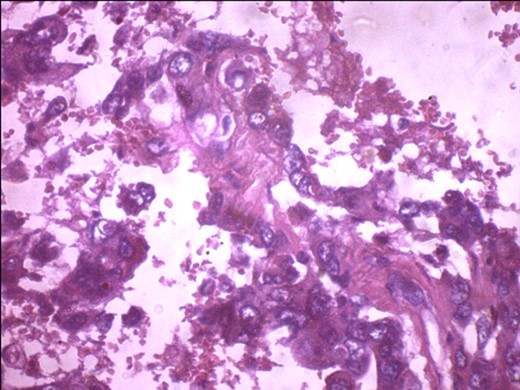

A 57-year-old woman presented with 5/12 history of left breast lump which gradually increase in size and became painful. Menarche was at 13 years without oral contraception. She had four confinements, the first being 20 years. Each child was breastfed for 8 months. No family history of breast cancer. Clinical examination showed breast asymmetry. Left breast was oedematous, shiny with extensive peau d'orange. Patient applied herbal preparations with multiple superficial skin excoriations. Outer quadrant breast mass was 8 cm, hard, with attachment to skin and underlying structures. No palpable axillary lymph node was felt and axillary ultrasonography, though desirable, was not done. Liver was not enlarged. Chest X-ray and abdominal ultrasound scan showed no involvement. Initial breast biopsy revealed an infiltrating atypical spindled tumour with hyperchromatic nuclei, which was both S100 and tyrosinase-positive. Tumour fungated with a darkly pigmented surface despite two cycles of neoadjuvant doxorubicin-based chemotherapy. Left simple mastectomy (Fig. 1) and axillary sampling (Fig. 2) of the sentinel and another slightly enlarged node were done, revealed a triple-negative invasive ductal carcinoma (Figs 3–6), with melanocytic differentiation (Figs 7 and 8), positivity for S-100 and patchy positivity for tyrosinase, an enzyme involved in melanin formation from dihydroxyl phenyl alanine. Only the sentinel node was involved, with the other showing reactive changes. Core biopsy of the tumour had ductal elements and was triple-negative.

Metastasizing glandular component of MBC, melanocytic variant, with few pigment deposits.